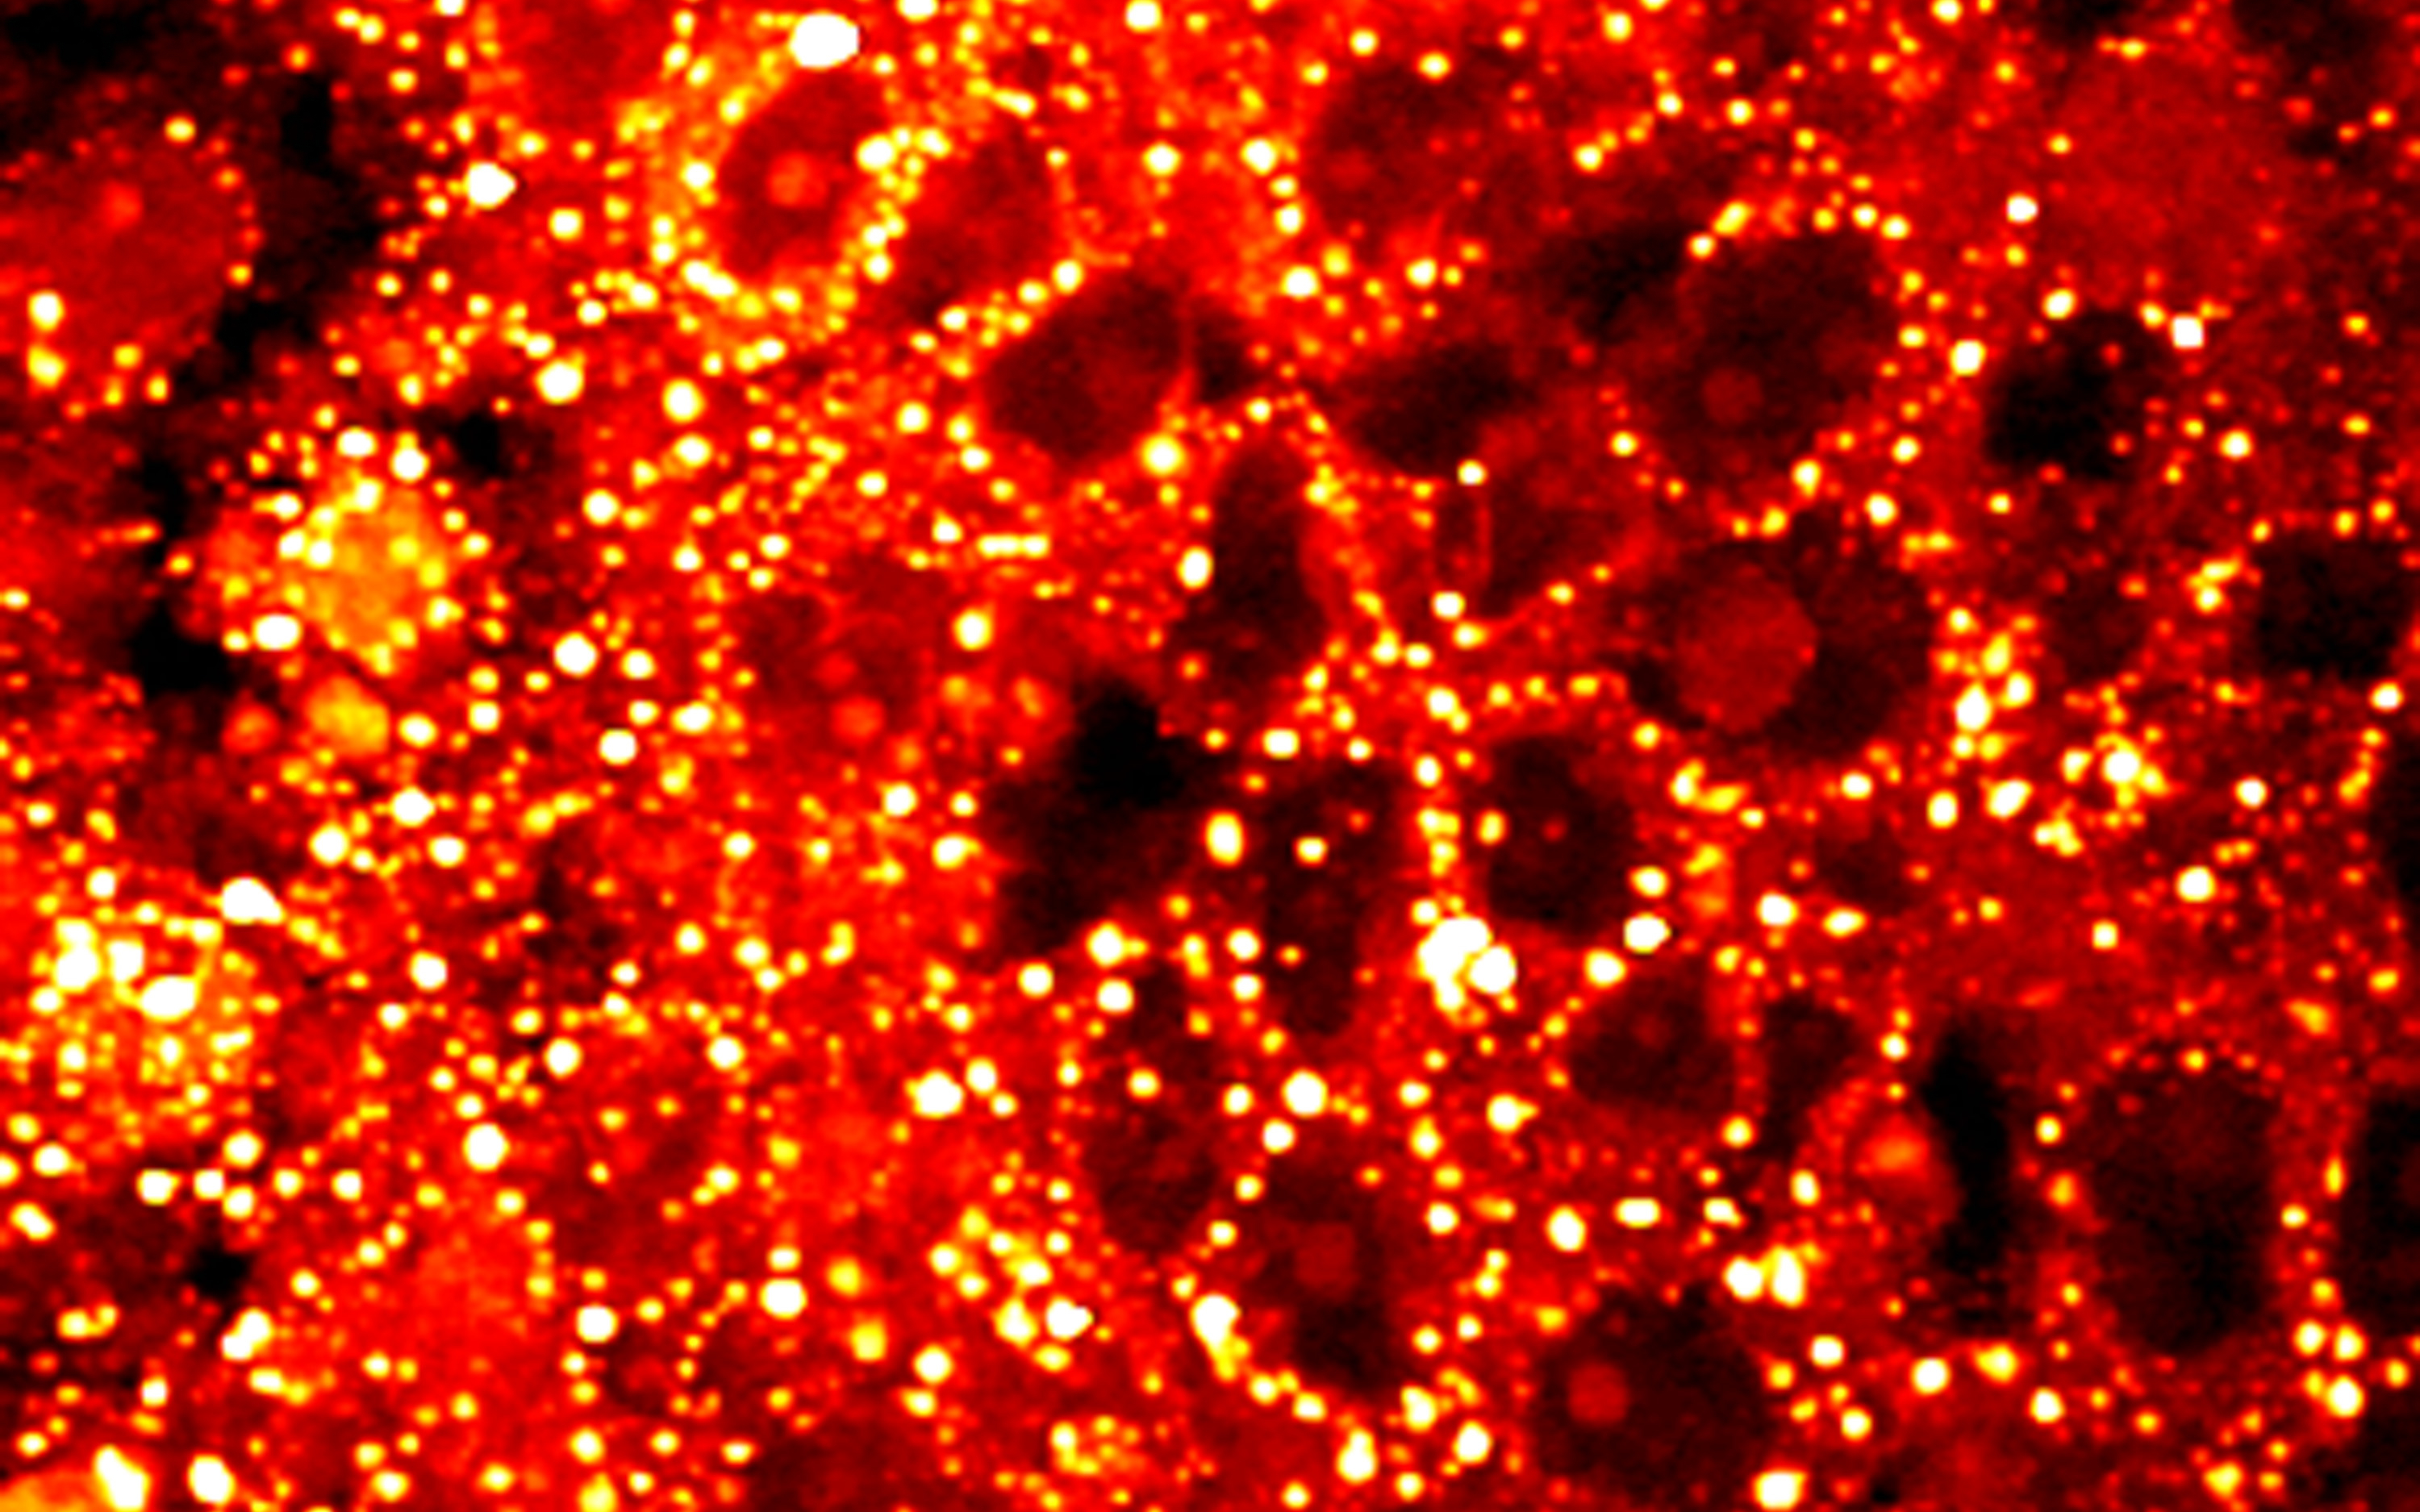

Abnormal lipid metabolism in prostate cancer. Credit: Ji-Xin Cheng, National Cancer Institute / Purdue University Center for Cancer Research

The Hippo/YAP and PI3K/mTOR pathways are active in the majority of malignant tumours, however until now we haven't known how they interact to control metabolism in cancer cells.

This research, published today in Developmental Cell, demonstrates they work together in cancer cells to rewire fat metabolism, which fuels tumour growth.